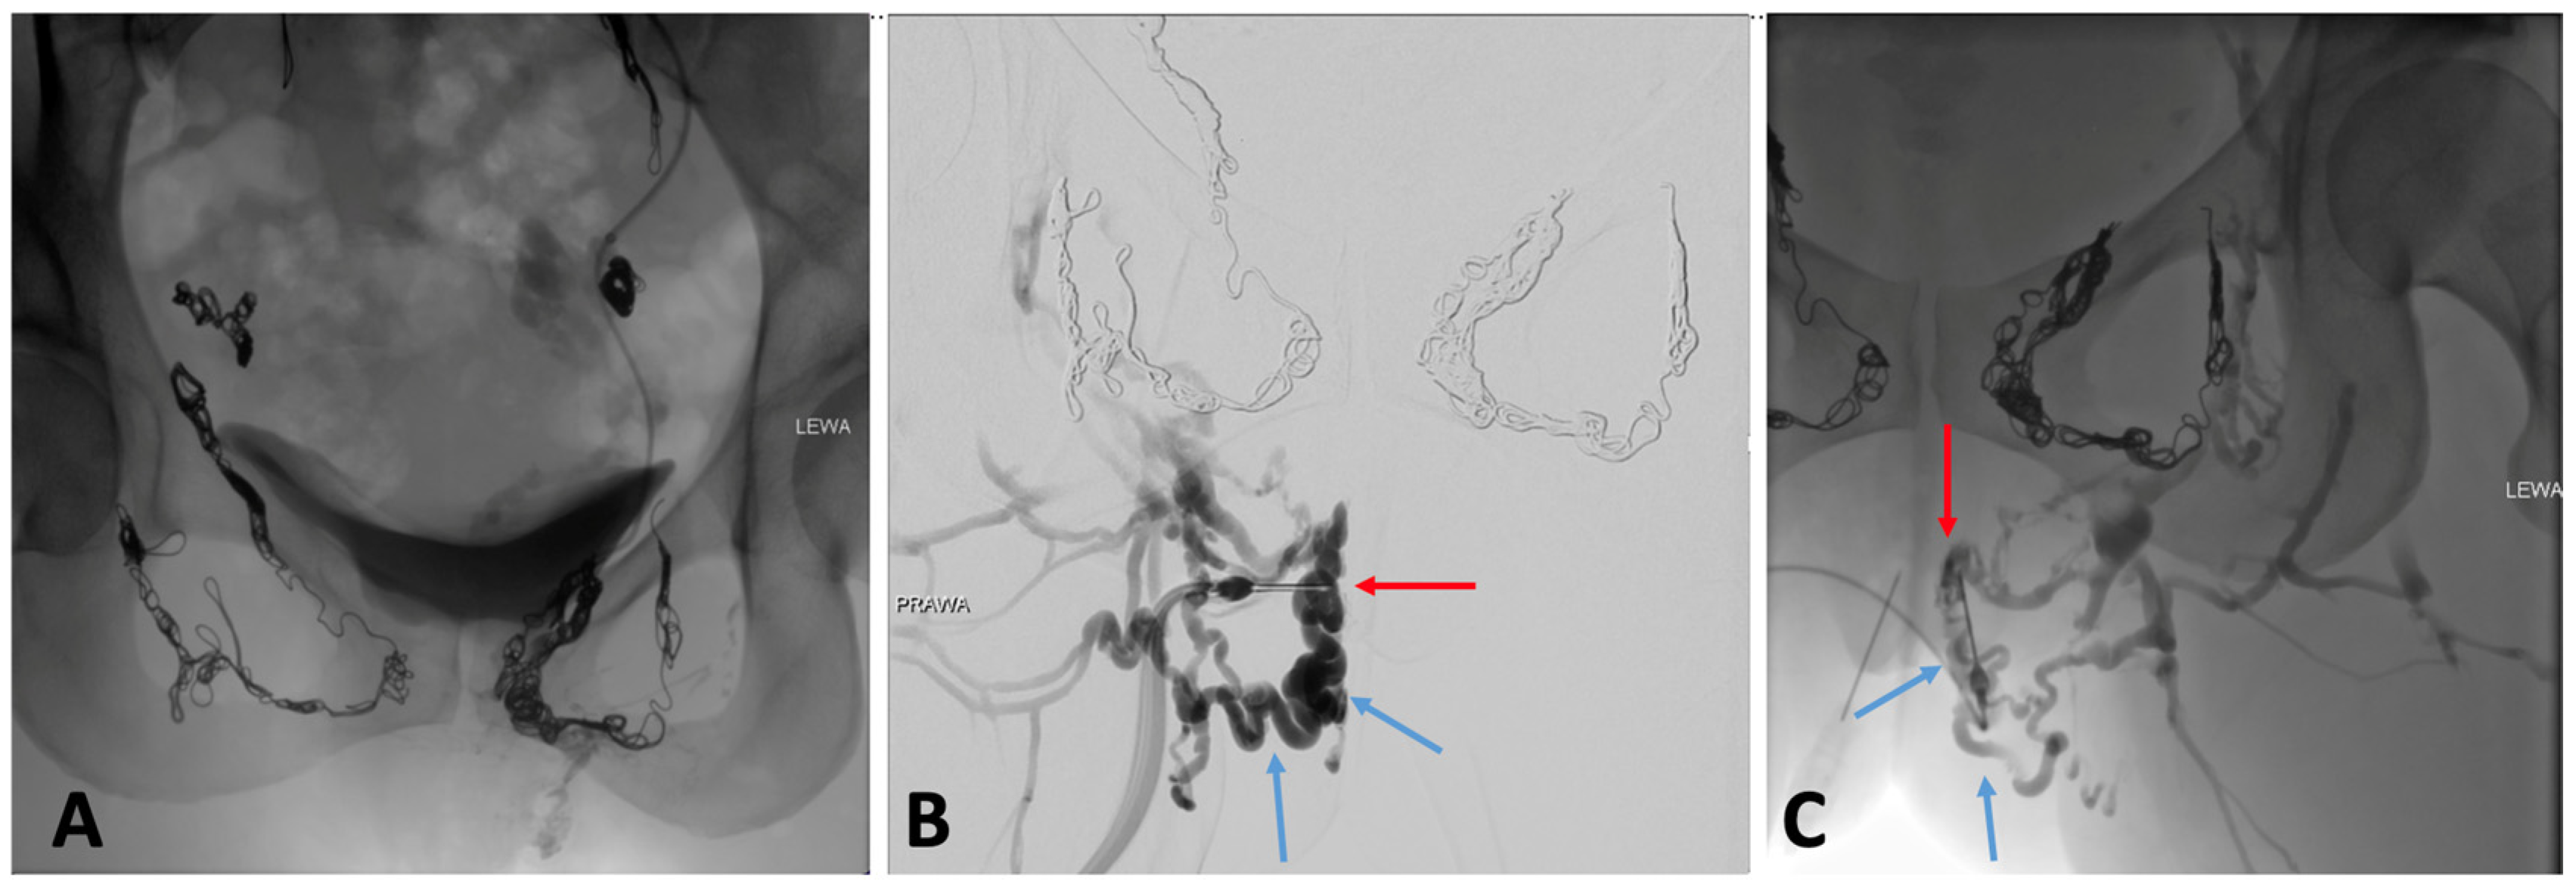

2.3.2. Catheter Venography and Intravascular Ultrasound